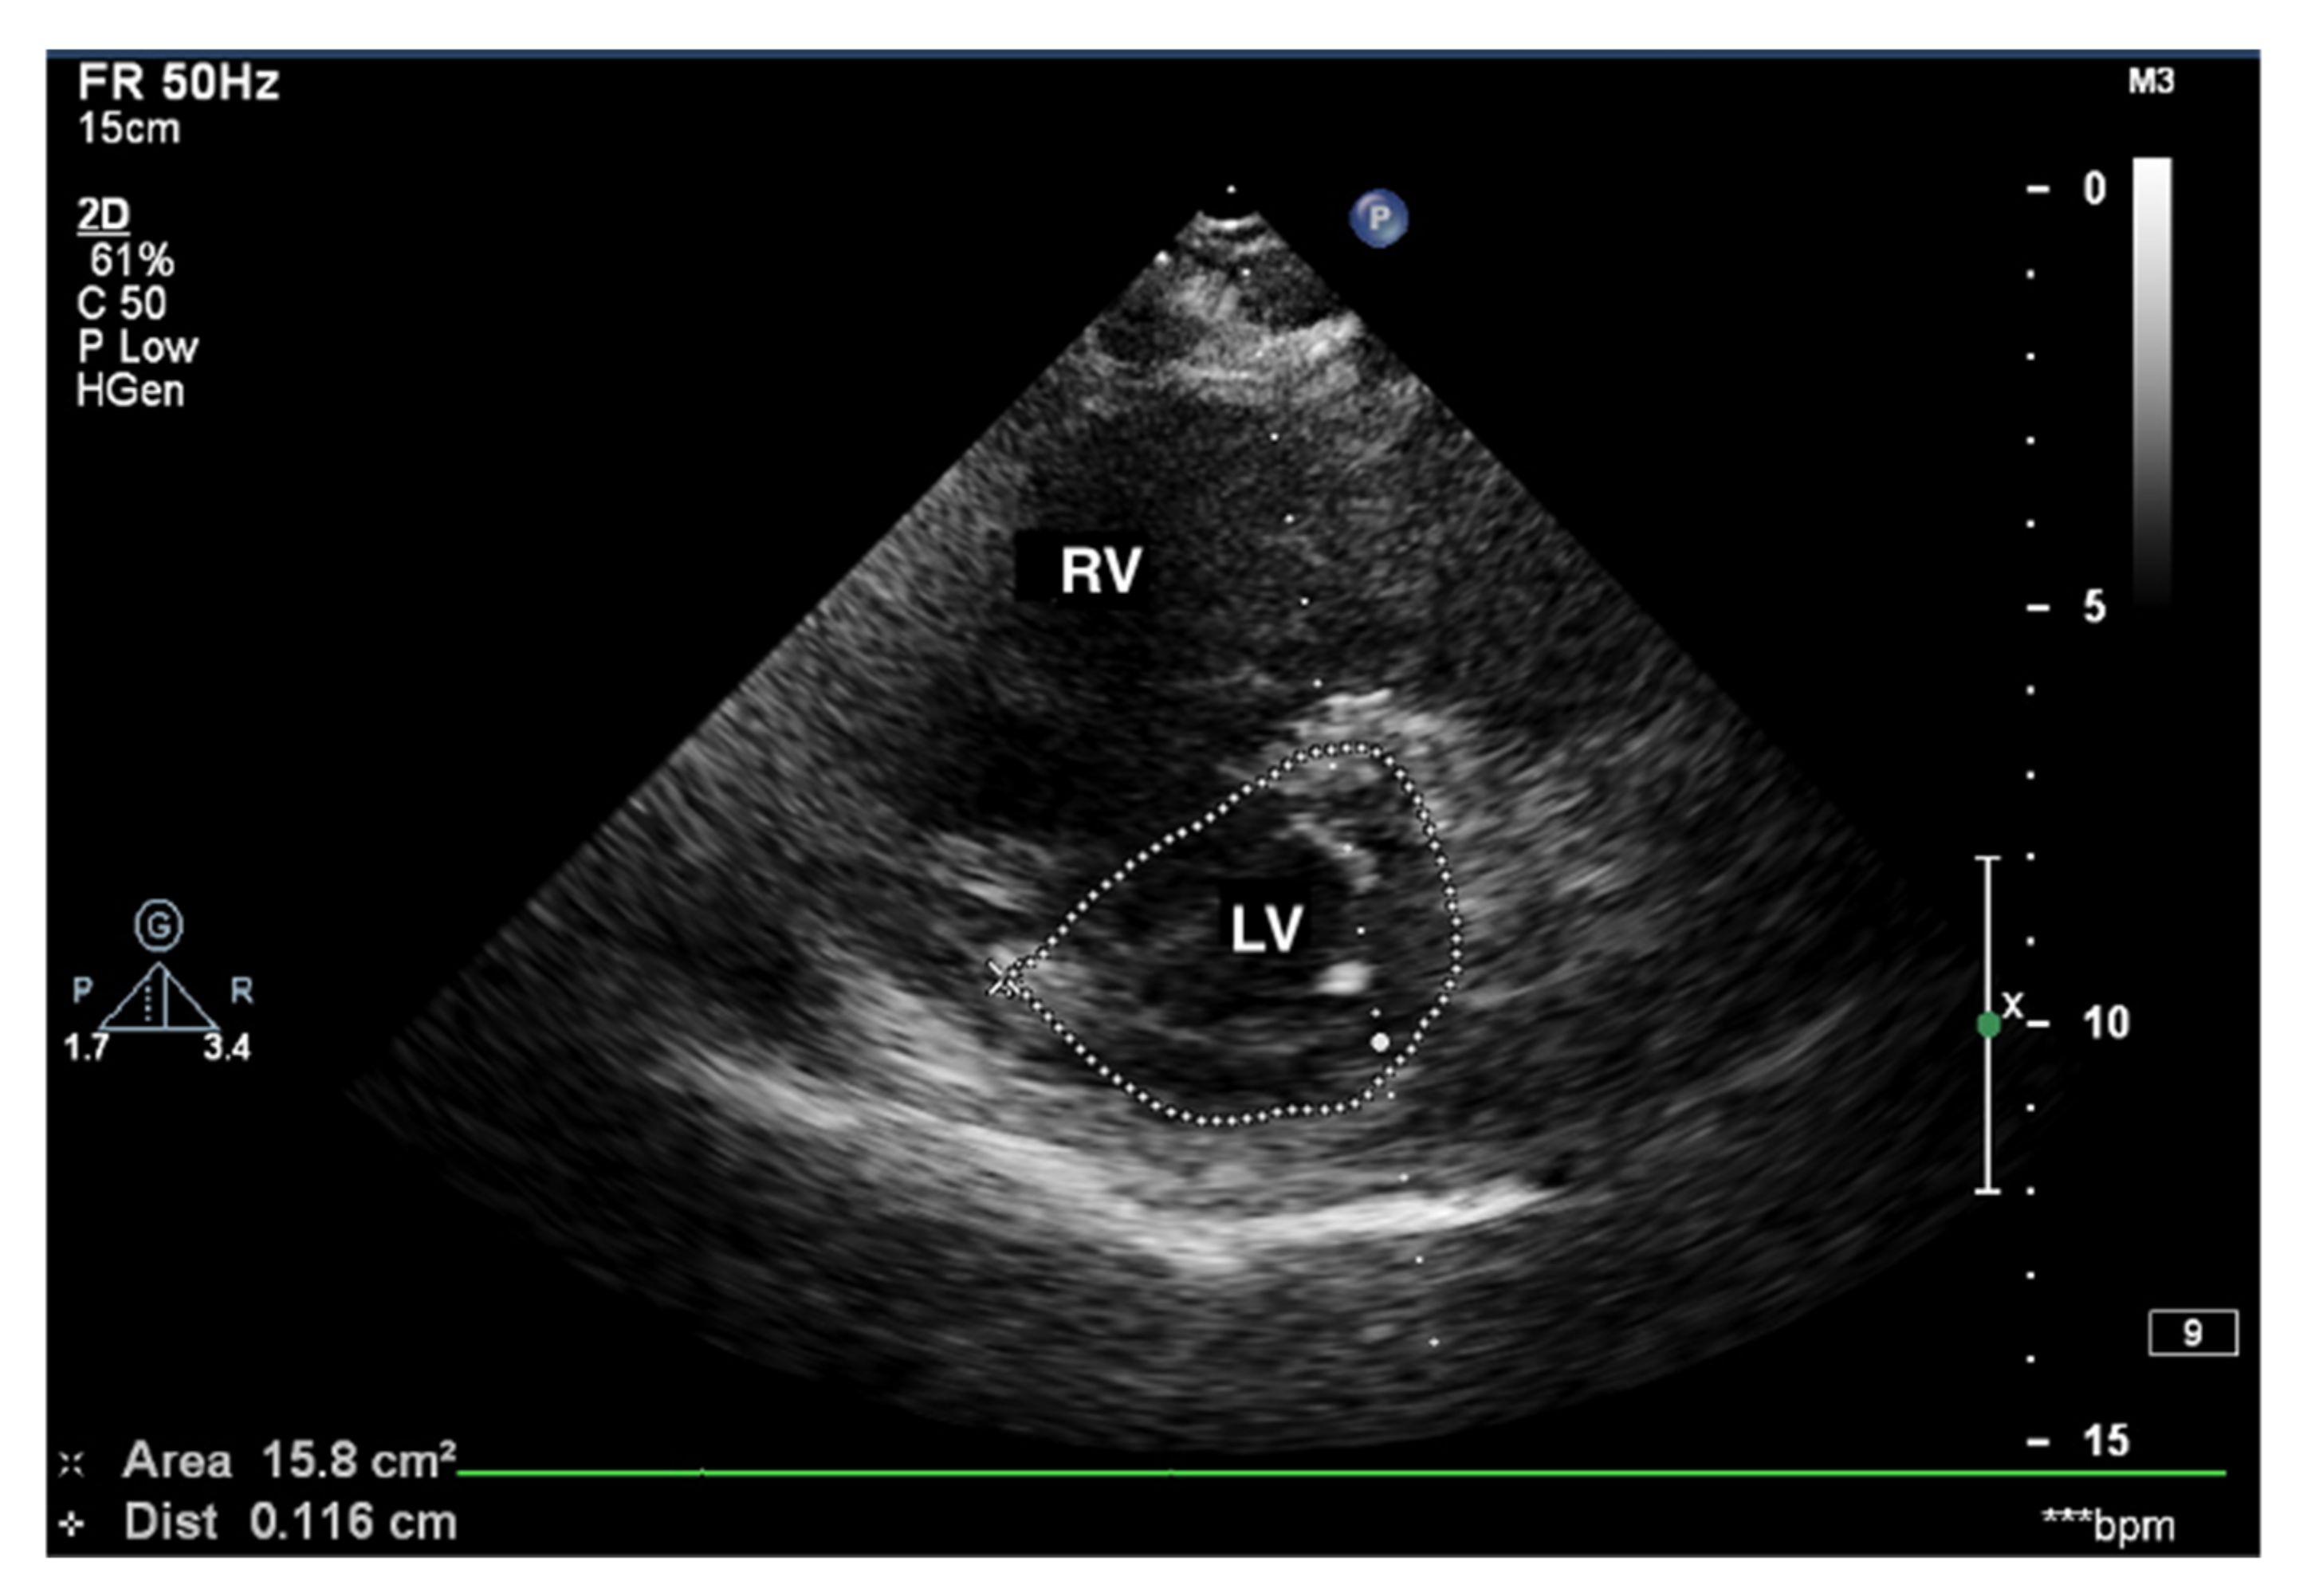

Figure 2.

Enlarged right ventricle. 2D-TTE, parasternal short-axis view (PSAX). RV: right ventricle, LV: left ventricle.

Transthoracic echocardiography (TTE) in a patient with advanced PAH is conspicuous by the RV cavity′s abnormal shape, especially in the parasternal short axis (Figure 5). The RV assumes a spherical shape, and the interventricular septum protrudes into the LV, forming the so-called D-shape sign [18]. If a D-shaped LV appears in the end-diastolic phase, it suggests RV pressure overload, whereas a D-sign shape in diastole suggests RV volume overload [19,20].

Figure 5.

D-sign, enlarged right ventricle, ventricular septum displaced towards LV. 2D-TTE, short-axis view (SAX). LV: left ventricle; 2D-TTE: two-dimensional transthoracic echocardiography.